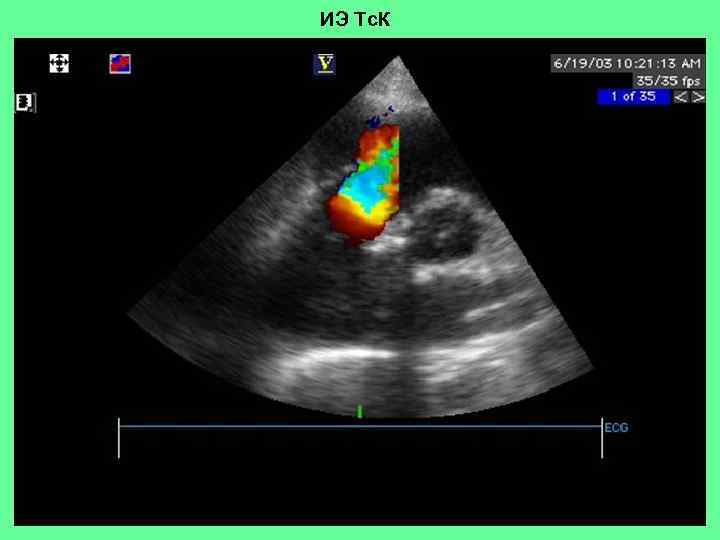

ИЭ Тс. К